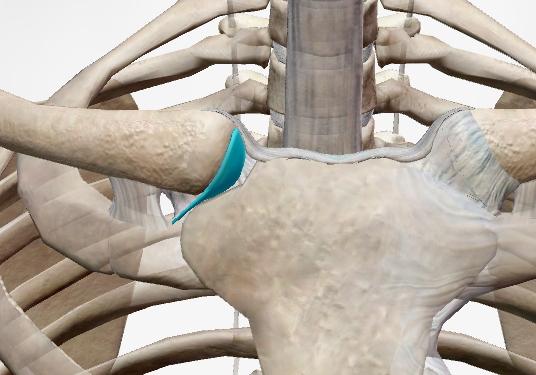

例えば、骨幹と骨端の間にある骨幹板や第一肋骨と胸骨柄を繋ぐ硝子軟骨がそれに当たります。

結合以外に【関節円板】と呼ばれるものは全て(椎間板、半月板、顎関節・胸鎖関節・手関節の関節円盤)は線維性軟骨です。